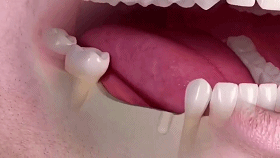

影响口腔功能。错颌畸形会影响咀嚼、发音等功能的发挥,比如影响牙齿的咬合关系,使得咀嚼效率不高,对食物的磨碎作用大大降低;有些患者牙齿咬不上,影响发音、说话等。如下图:

牙齿长成什么样需要矫正?